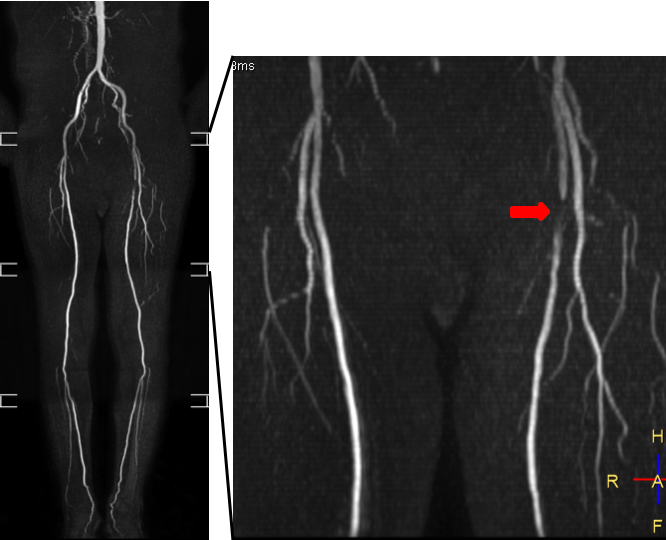

非造影下肢動脈 MRA:造影剤を使用せずに腹部から下肢動脈が描出されており,左浅大腿動脈に狭窄(矢印)を認めます.